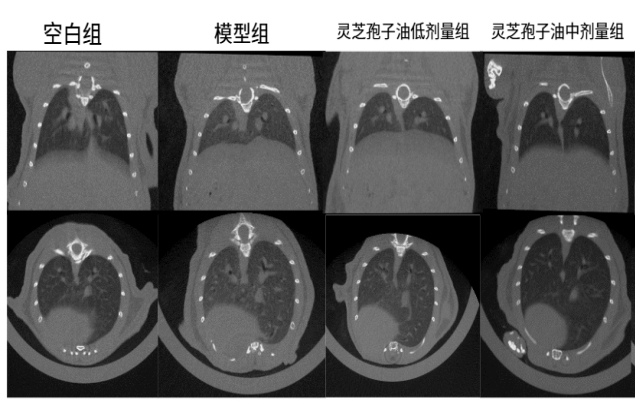

體內功效實驗研究結果表明:在為期52天的小鼠實驗中,每日6粒廣藥牌靈芝孢子油,靈芝孢子油顯著減少了肺部肉芽腫結節(jié)的面積(減少23.07%)和磨玻璃陰影,降低炎癥因子和趨化因子水平 ,證實廣藥牌靈芝孢子油具有一定的防治小鼠肉芽腫型肺結節(jié)的作用。

圖:靈芝孢子油對肉芽腫型肺結節(jié)小鼠肺部斷層掃描檢測結果及統(tǒng)計

體內作用機制研究證實:通過調節(jié)PI3K-Akt-mTOR信號通路、抑制p-AKT和p-mTOR活化、糾正代謝紊亂、減少炎癥因子和趨化因子的釋放,最終達到緩解肉芽腫型肺結節(jié)的效果。